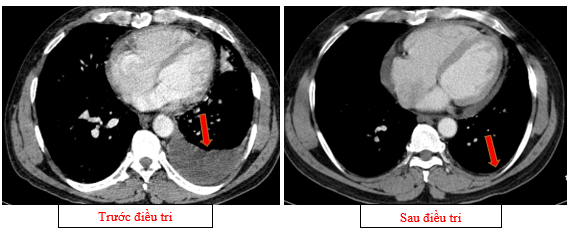

Hình 03: Màng phổi trái có vài nốt đặc ngấm thuốc nốt lớn nhất kích thước 17x15mm Khoang màng phổi trái có dịch dày 54mm

Hình 09: Không còn tổn thương tràn dịch màng phổi trái trên phim chụp